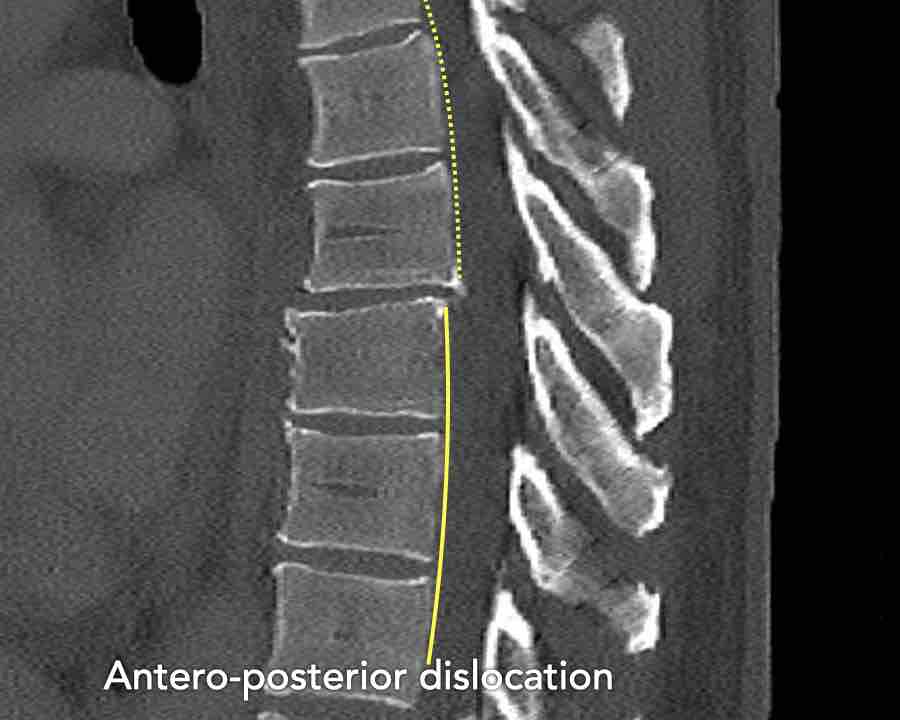

Type C Translational injuries

We start with the most severe injury and work from there.

Translational injuries are dislocation or displacement of a vertebral level from the level below or above.

There are no subtypes because various configurations are possible.

There is a high degree of instability and therefore an indication for surgery.

This is a clear example of translation in the anterior direction.

Conclusion

Type C injury.